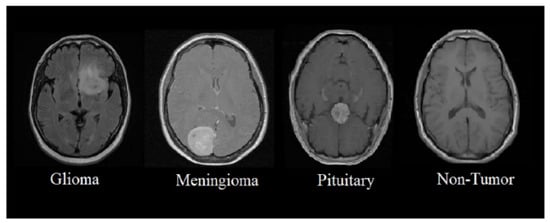

3.2. Dataset

4. Results

4.1. Performance of Simple EfficientNet-B0

4.2. Performance of Fine-Tuned EfficientNet-B0